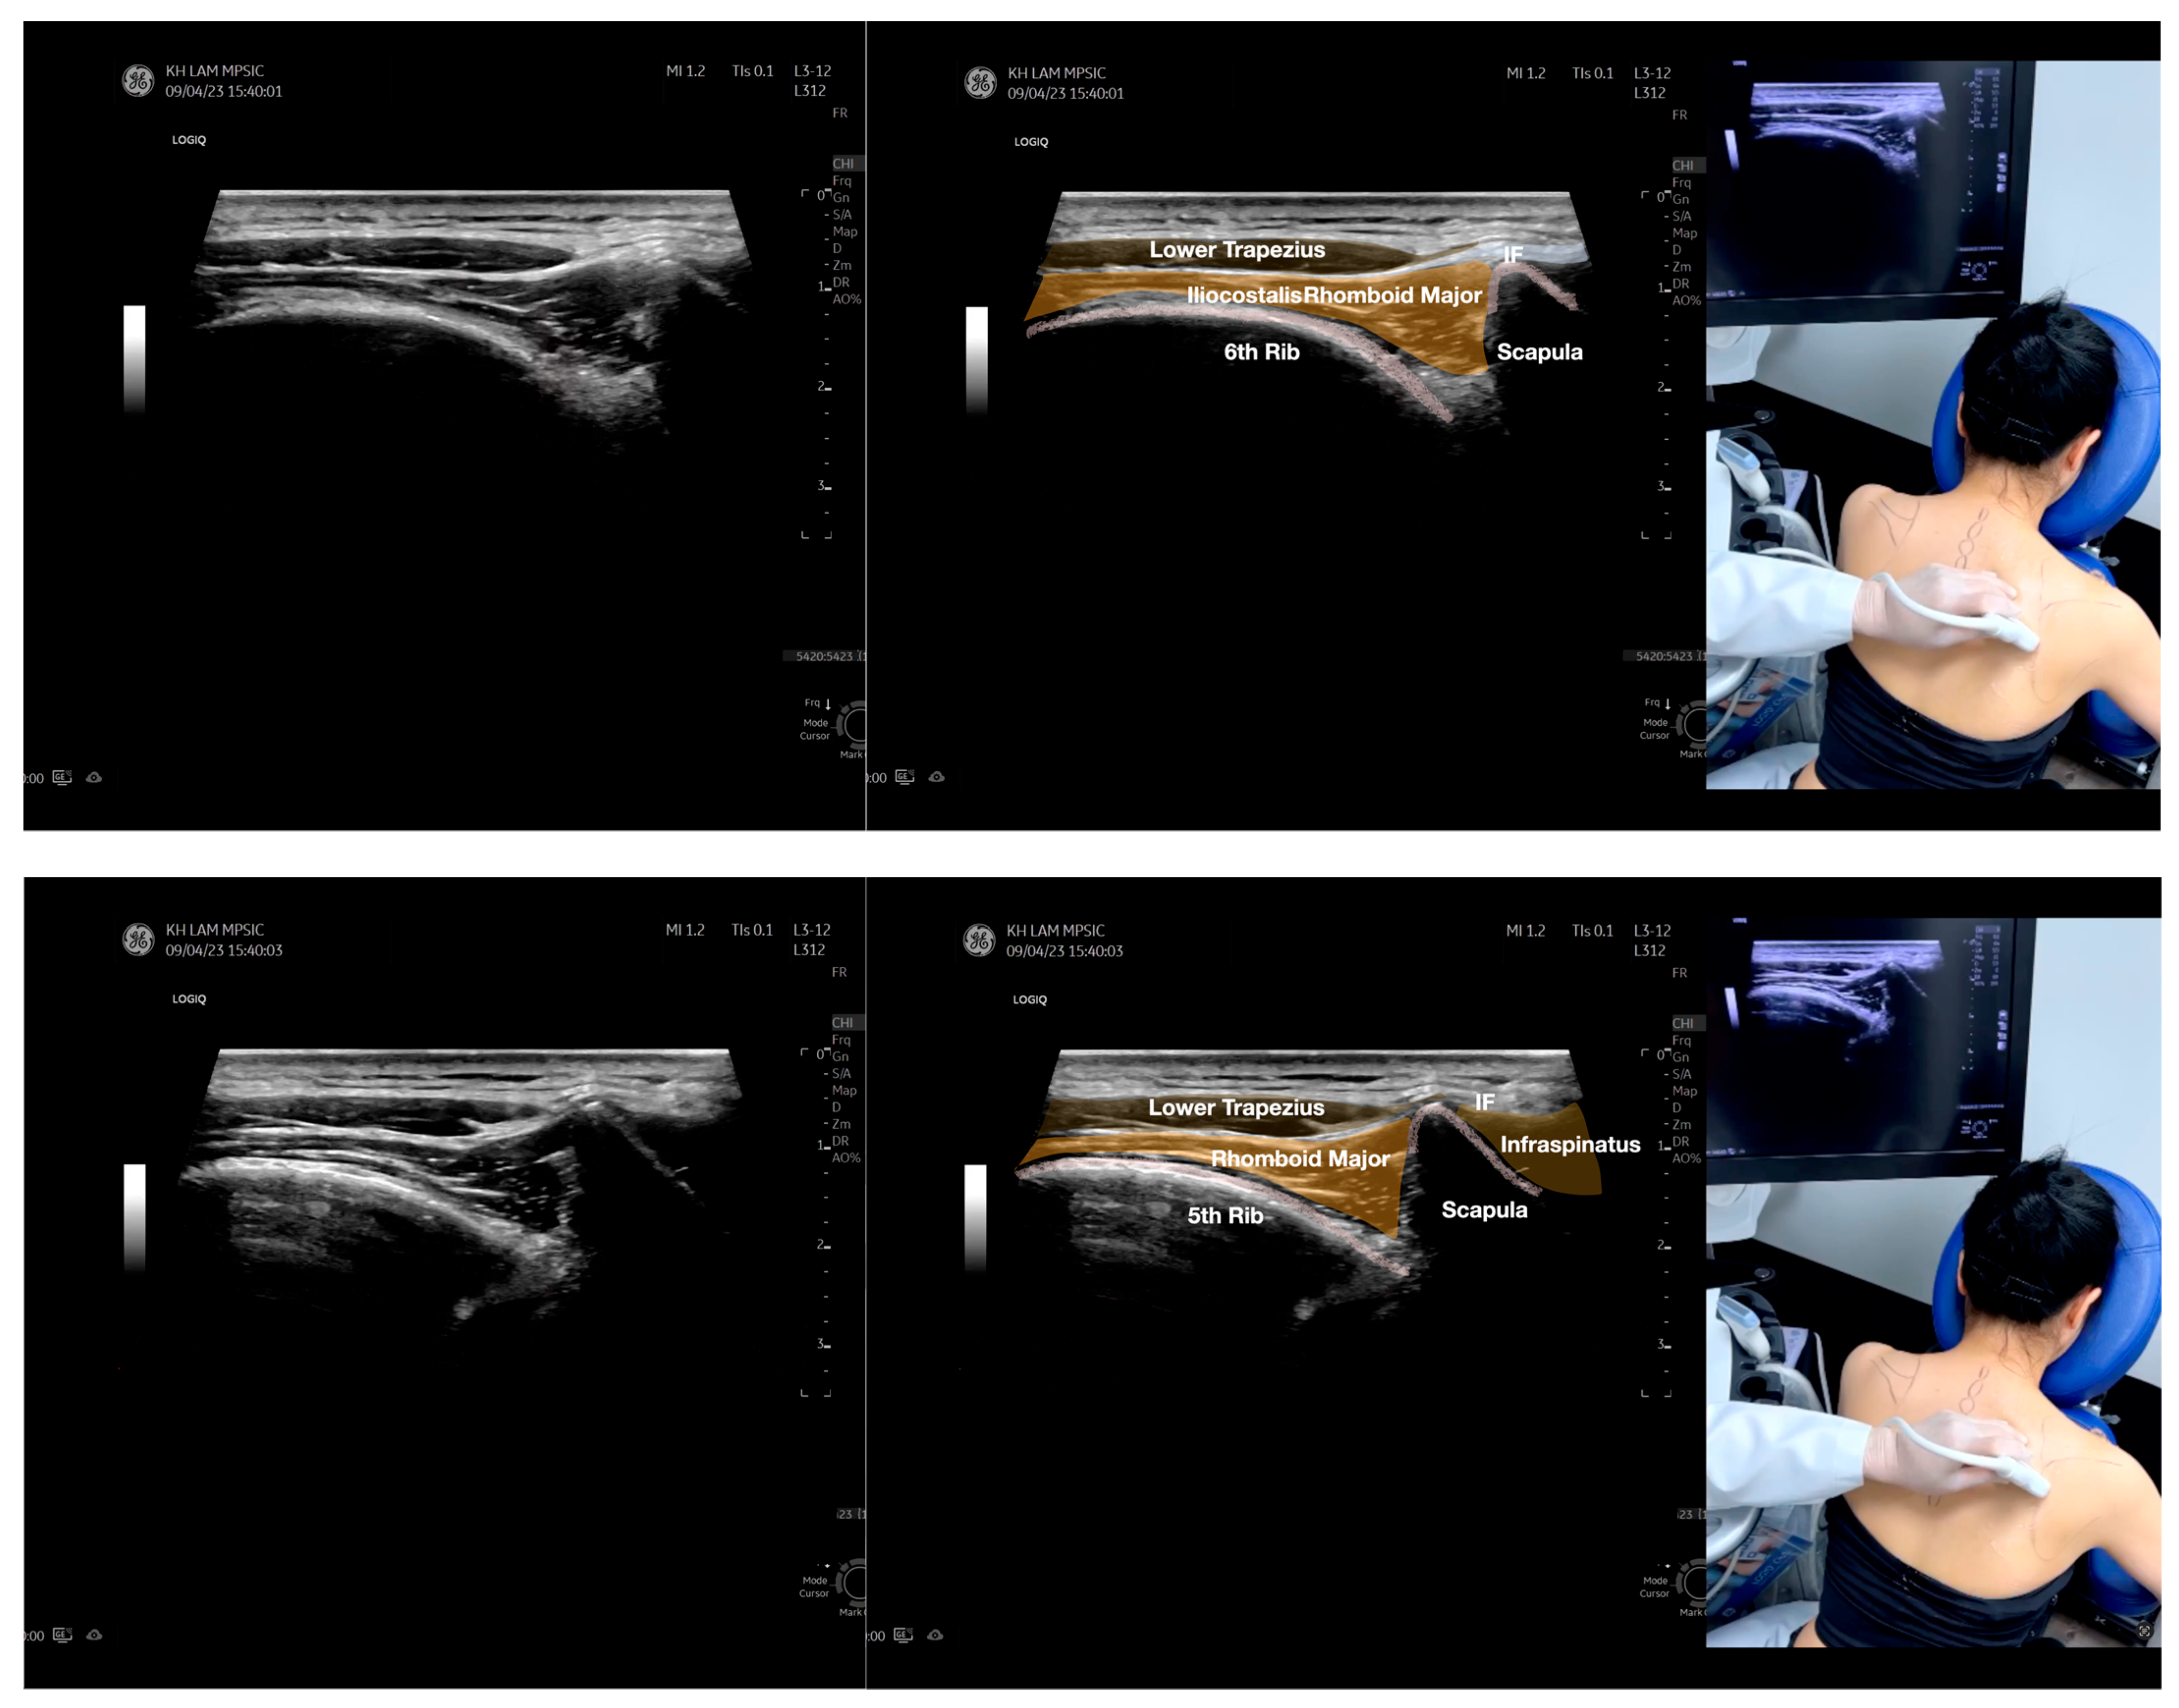

Figure 5.

Sonoanatomy of scanning the infraspinatus fascia in the sagittal plane from the rhomboid minor laterally, then back to the rhomboid major. The step-by-step scanning techniques of the structures illustrated in this figure have been shown in Video S9. Available online: https://www.dropbox.com/s/gu9hhrdq9erin6n/Figure%205.docx?dl=0 (accessed on 1 January 2023).